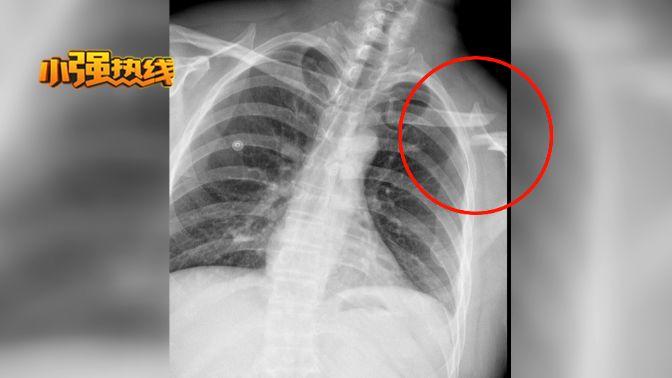

当天吴先生被确诊为

左锁骨粉碎性骨折

手术后,吴先生骨折处植入了一块钢板,11天的住院治疗共花费了1万7千块钱。吴先生认为,这笔医药费应该由杭州蜂之语公司承担。因为,当时就是这家公司雇佣了他,让他运送风筝。